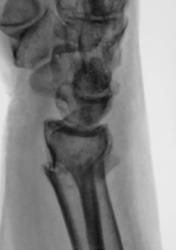

Травма. направлен на рентгенографию лучезапястного сустава

Поперечный перелом луча в типичном месте с разгибательной (сколько-то градусов) деформацией оси, боковым смещением на ширину кортикала, захождением ≈ 4 мм, перелом ШОЛК с/с.

Для оценки кистовидно измененной полулунной кости и исключения "дыр" в основании 4 пястной кости... укладку и центровку на кисть - и картина, возможно, поменяется)).